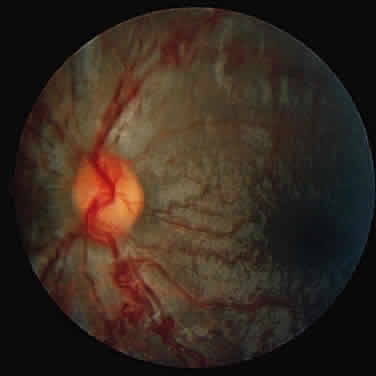

A unique retinal abnormality, the macular halo syndrome, has been reported in type B NPD by Cogan and Kuwabara135 and consists of a ring of opacities around the macula that causes no visual impairment (Fig. 15). This abnormality has been reported by several authors.141–143The crystalloid halo which measures about half the disc diameter occurs at the outer edge of the retina mainly in Henle's fiber layer causing only minor obstruction of the overlying vessels. Matthews and associates144 proposed that the macular halo represents the mildest form of a cherry-red spot in the ganglion cell layer of the retina. Their findings are in conflict with those of Cogan et al.138 The precise location of the opacities in the retina remains uncertain because of the lack of histopathology. The available clinical data suggest that such opacities are permanent.

Fig. 15. Macular halo in a patient with Niemann-Pick type B.